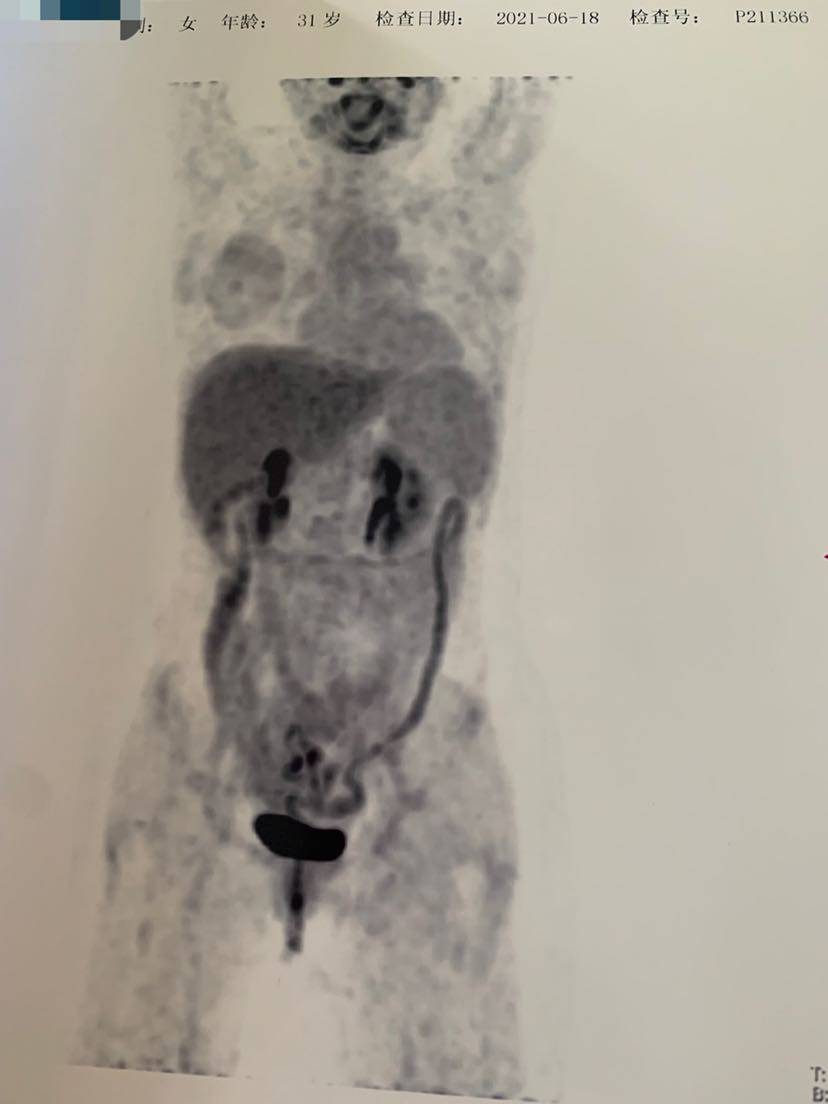

自从2020年3月确诊肺癌IV期以来,从病危到现在的CR,这次确诊15个月,入院做了个大检查,pet ct以及全套肿标,增强脑核磁,心脏彩超以及血常规等,一线阿来后,没有任何的副作用,甚至连个皮疹都没有,但是阿来的对我的效果却是极好的。确诊后每两个月一次胸部平扫➕腹部b超,一个月一次肝肾功能(10个月后由于每次都正常,后面自己也偷懒2个月一次),肿标吃药第一个月查过一次cea后面就再也没有跟随的去看过,体感一直是好的,下面附一次本次的检查单,好转看得见,继续保持啊……

发帖不通知………😡 你果然不出意外 不负众望 众望所归的CR 这个PET只为几张纸证明一下😁

恭喜啊,影像学CR啦!